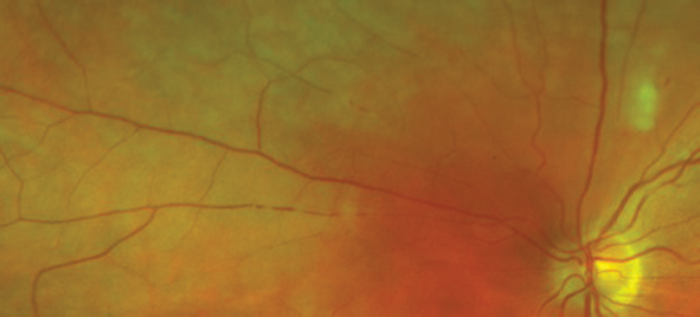

A 29-year-old woman presented to the emergency department with a two week history of floaters and patchy peripheral visual field loss in the left eye (LE). She had no relevant medical history and she was not on any current medication. On ocular examination, visual acuity (VA) was 6/6 in both eyes (BE). Anterior segment and intraocular pressure were normal. Right eye (RE) fundal examination was unremarkable and LE fundal images are shown in Figures 1a and 1b, as well as the corresponding LE fluorescein angiography (FA) on Figure 2. Some weeks later she started to notice similar symptoms in her RE but VA remained unaffected. Funduscopy and FA images are shown in Figure 3.

Figure 1a: LE funduscopy at presentation.

Figure 1b: LE fundus on closer examination of branch retinal arteries nasal to the optic disk.

1. Figures 1a and 1b show signs of retinal occlusive microangiopathy with areas of branch retinal artery and arteriolar occlusion. Note the accompanying areas of retinal ischaemic oedema. Figure 4 shows silver-wiring signs on a major arteriole. This is a late common vascular feature after complete vascular shutdown.

2. In Figure 2 note the delay of fluorescein filling in some of the branch retinal arteries and how the late phases reveal segmented hyperfluorescence as well as complete shutdown of peripheral arterioles especially in the temporal region. In Figure 3 note the caliber narrowing of some of the branch retinal arteries and arterioles on the fundal picture and how the FA show areas of patchy vessel hyperfluorescence not seen on funduscopy.